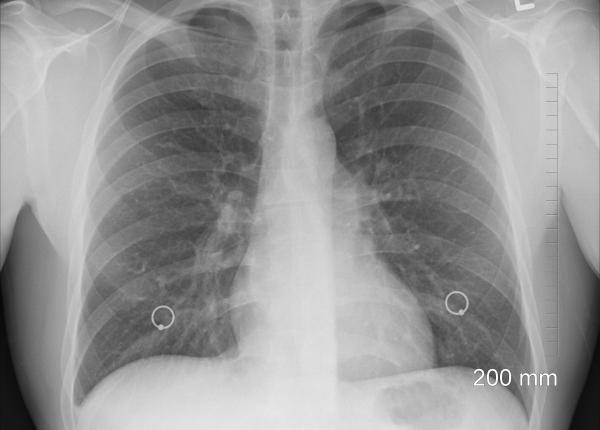

Prof. dr. Ruxandra Ulmeanu vorbește la Interviurile Dc Medical despre bolile cauzate de poluare și fum. Weekendul trecut au fost zeci de incendii în mai multe județe din...